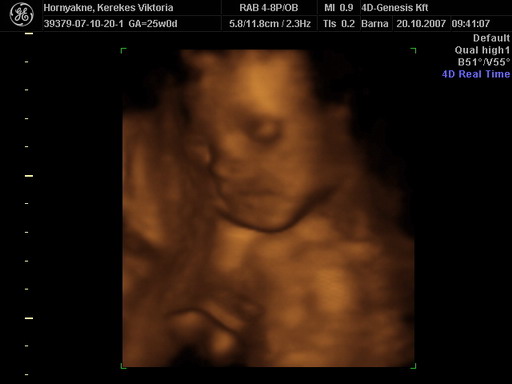

Jó sokat írtatok. Na most viszont teszek fel képet.

Íme:

Kép

Remélem jól látszik, hogy kisfiú lesz. :lol: